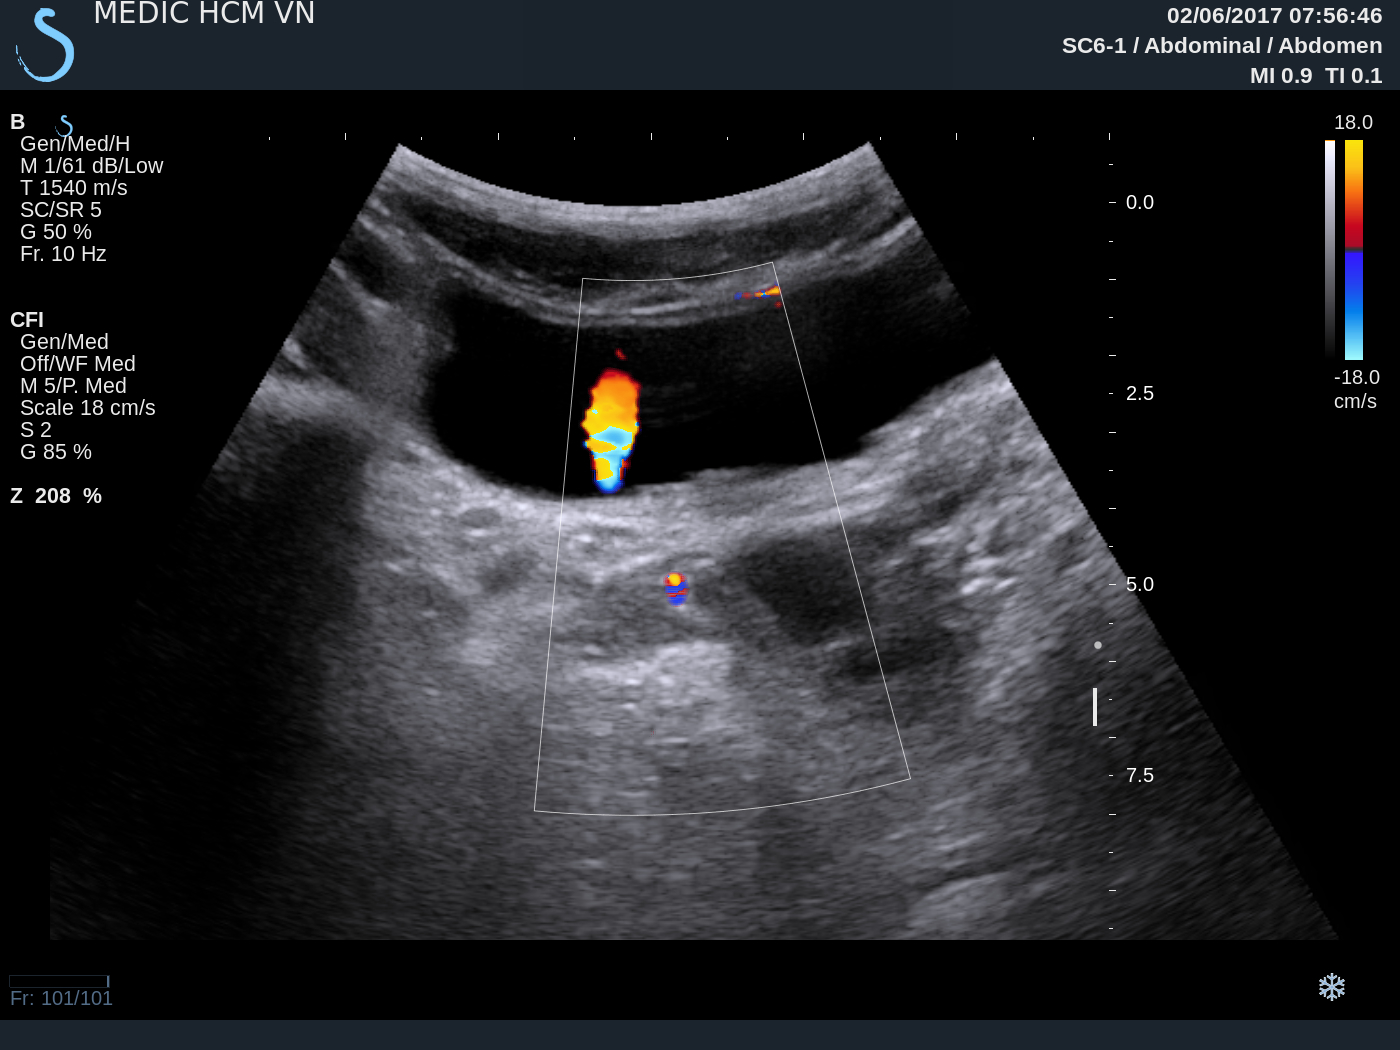

From www.ultrasoundmedicvn.com

VIETNAMESE MEDIC ULTRASOUND CASE 436 SOLITARY KIDNEY, Dr PHAN THANH Urine Jet Ultrasound Routine ultrasonography (usg) usually relies on the morphological change (tapered appearance of lower ureter) for the diagnosis of megaureter. This study was designed to investigate a variety of sonographic features of ureteric jets in order to define patterns of flow. The intravesical ureteral jets, or the bladder jets represent the sonographic appearance of discrete boluses of urine entering the bladder,. Urine Jet Ultrasound.